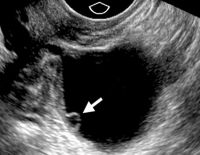

Thực hiện siêu âm canh trứng có ảnh hưởng gì không?

Siêu âm canh trứng để làm gì? Có ảnh hưởng gì không? Đây là phương pháp được ứng dụng nhiều trong điều trị vô sinh – hiếm muộn ở nữ giới. Và để trả lời cho những thắc mắc về siêu âm canh trứng, hãy...